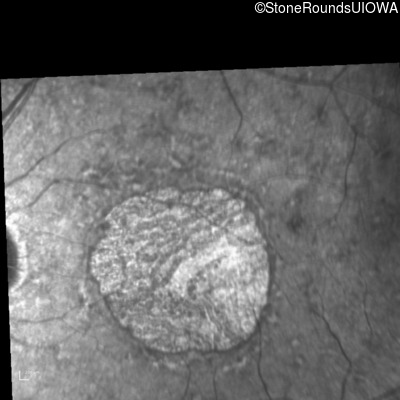

Infrared Fundus Photograph - Right - 20/80 -1

Exemplar